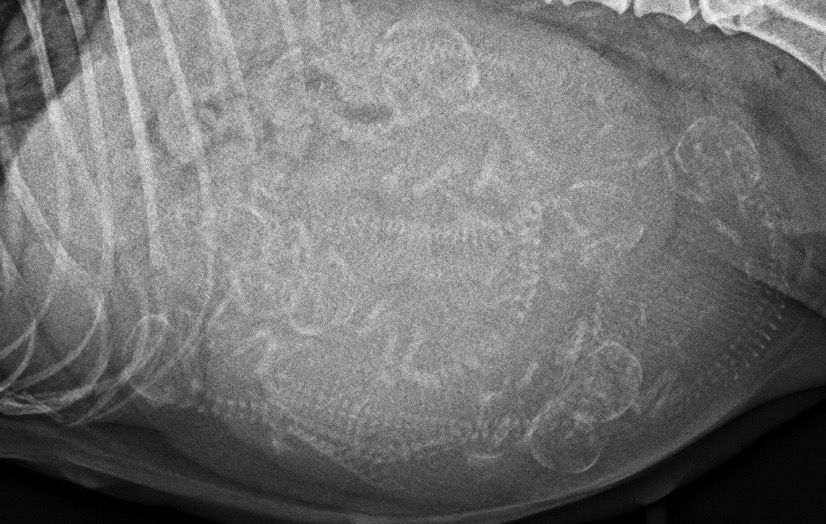

Wir entschlossen uns zur Sicherheit zu einem Röntgen an Tag 55 und mussten feststellen, dass wir nicht nur 1-2 Welpen nicht gesehen hatten, sondern 3-5.

Aber auch das Röntgenbild lässt keinen 100% Schluss auf die genau Zahl zu, denn die Welpen können übereinanderliegen.

Wir vermuten also im Moment, dass es 8-10 Welpen sind.